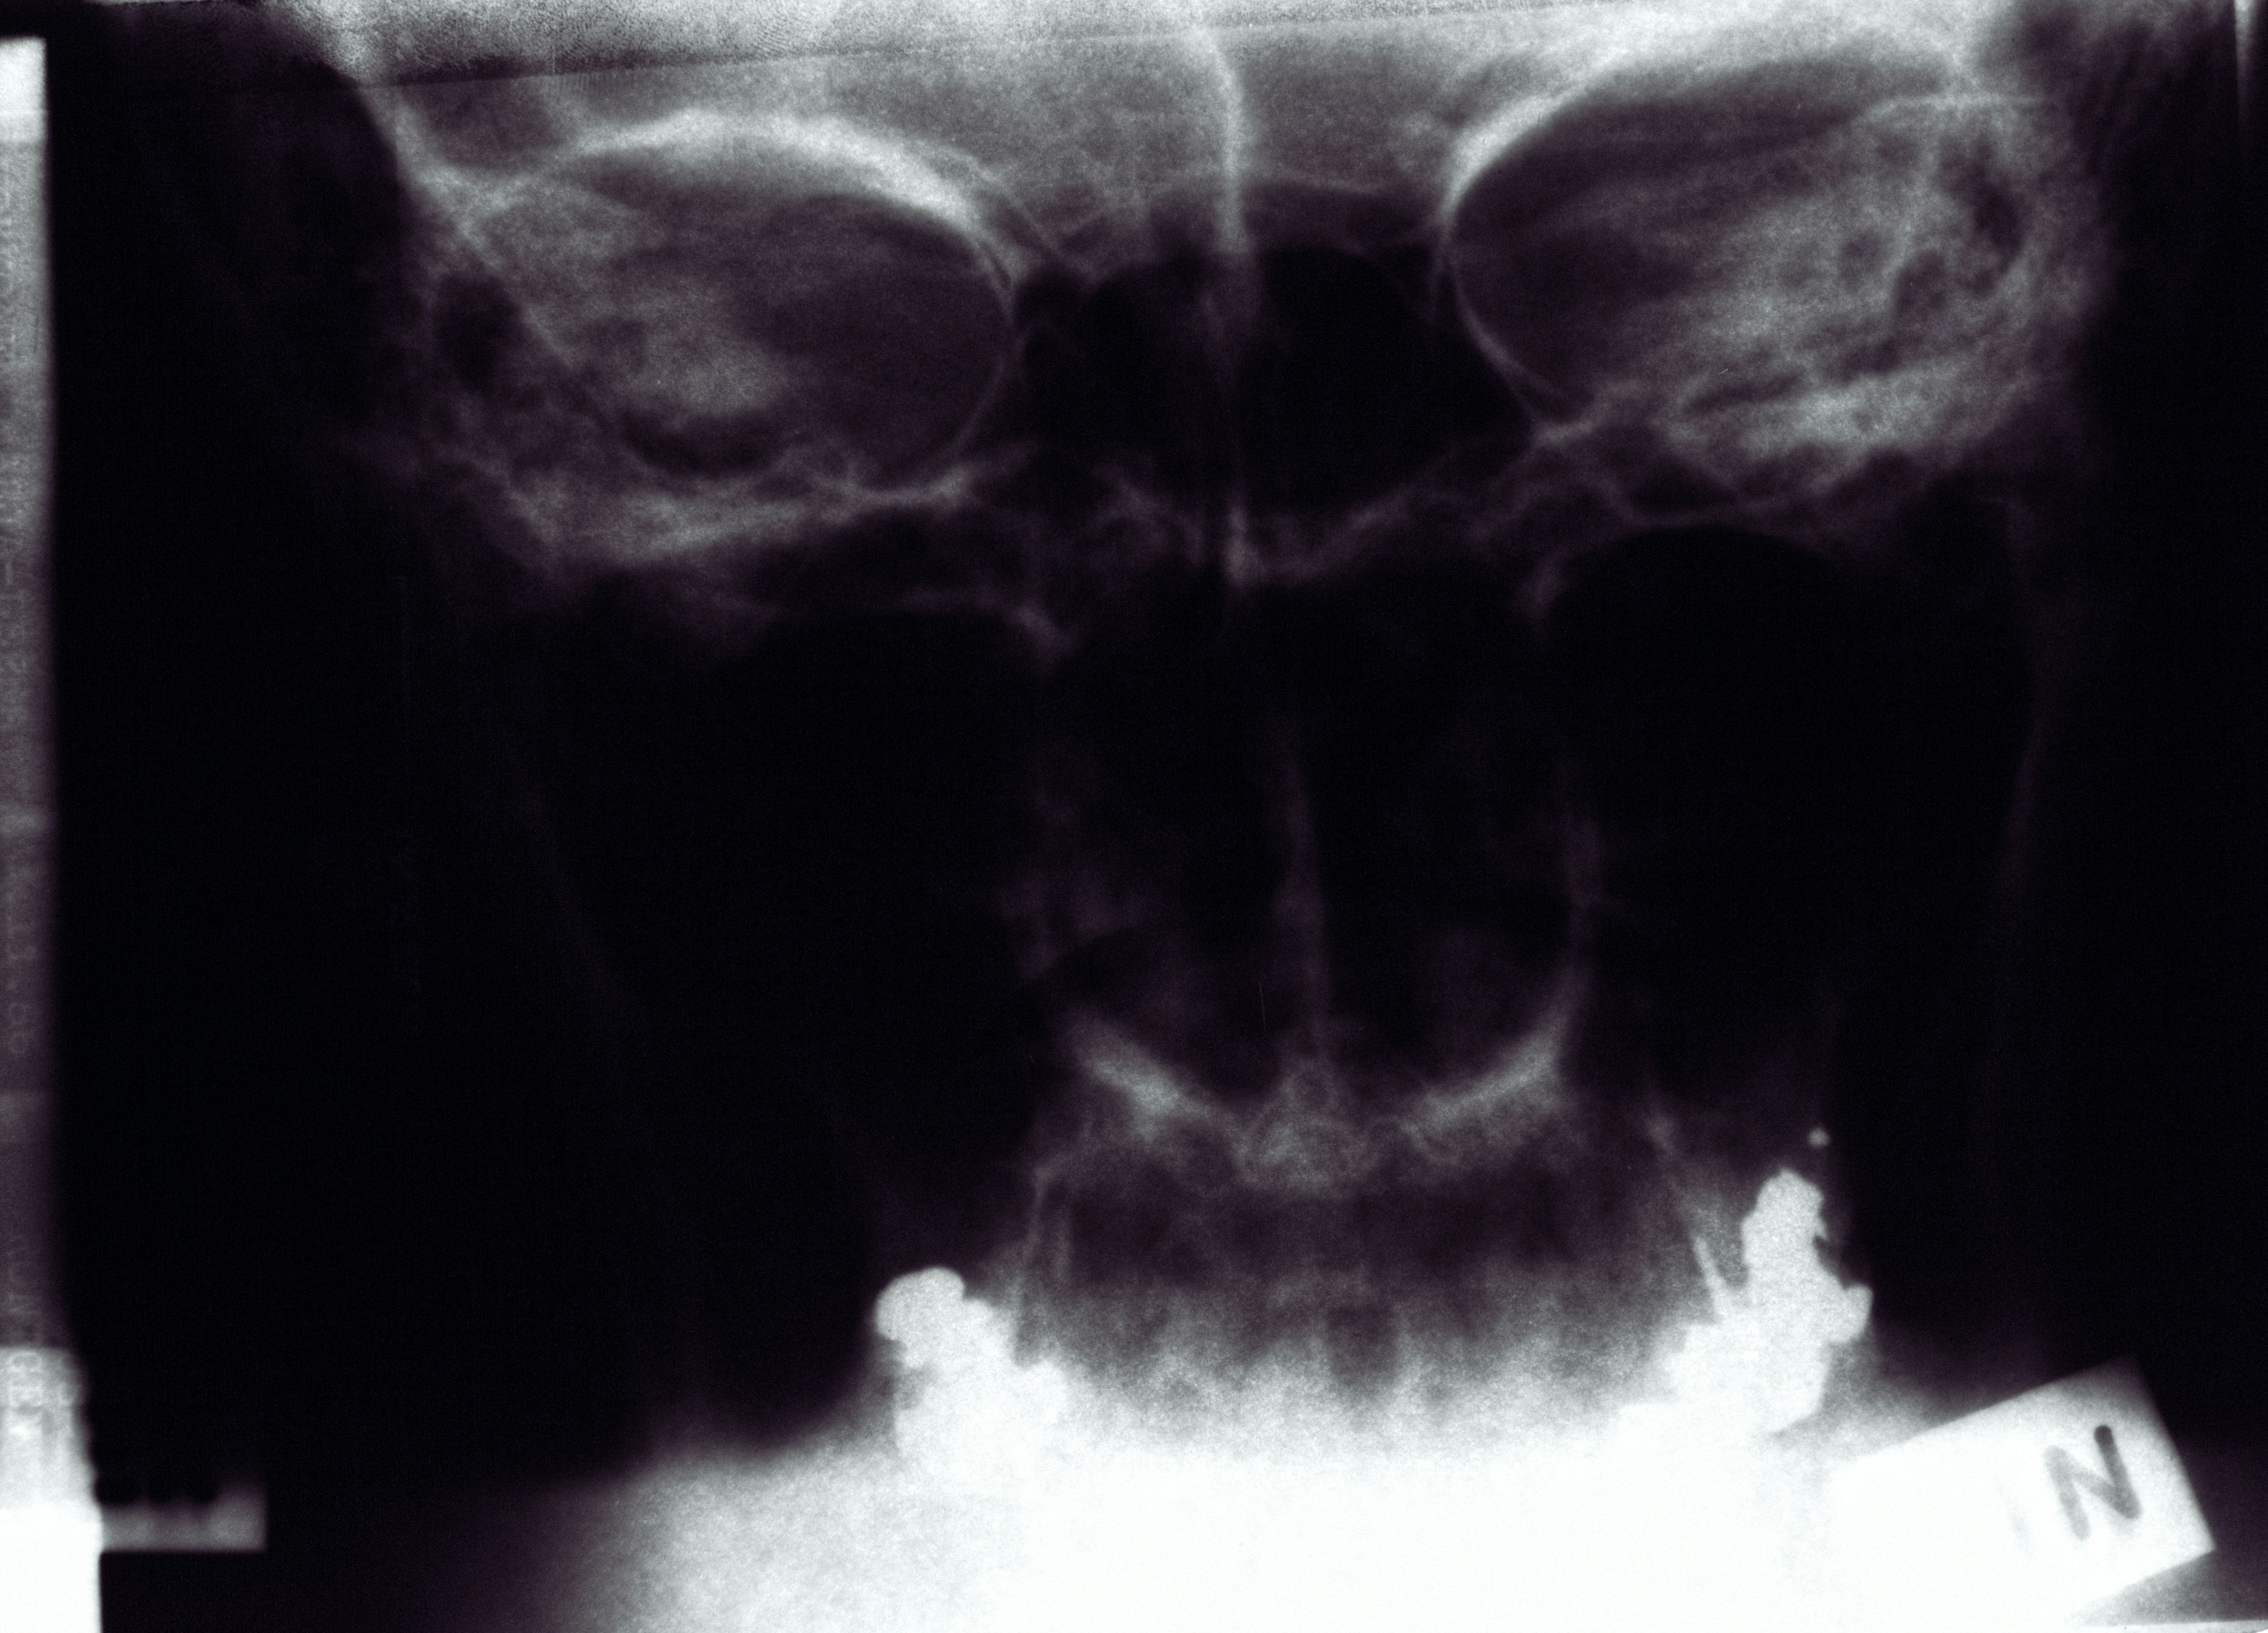

- 첫 방문: 염증 부위 확인 → 마취 → 치아 뚫기 → 신경 제거

- 두 번째: 내부 청소 → 약 넣기 → 임시 봉합

- 세 번째: 상태 확인 → 충전재로 채우기 → 보철(크라운) 준비